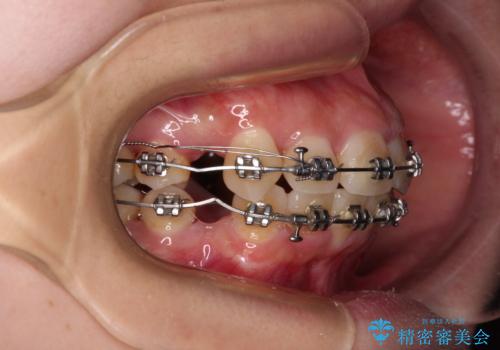

下顎前歯が隠れて突出した口元 ワイヤー装置での抜歯矯正

- 矯正装置

- メタルブラケット

- 治療計画

- 前歯のデコボコと口元の突出感を気にして来院された患者様です。

下顎骨の左右差や、上顎骨の前方位などが認められたため、上下左右の第1小臼歯4本を抜歯し、ワイヤー装置にて矯正治療を行うこととしました。